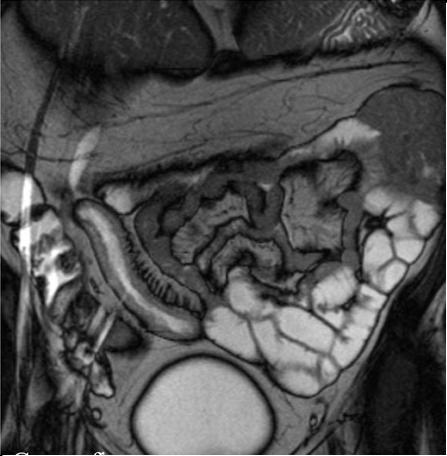

Aspect de grele inverse . :Perdre etendue

de villocite de tout jejunum ( fleche rouge )et la

jejunisation de ileon ( fleche jaune ) . Image

TDM en coupe coronal |

| Aspect a jejunisation de

ileon dans maladie coeliaque . Signe de " grele

inverse" Image TDM en coupe axiale a

travers de la region pelvienne |